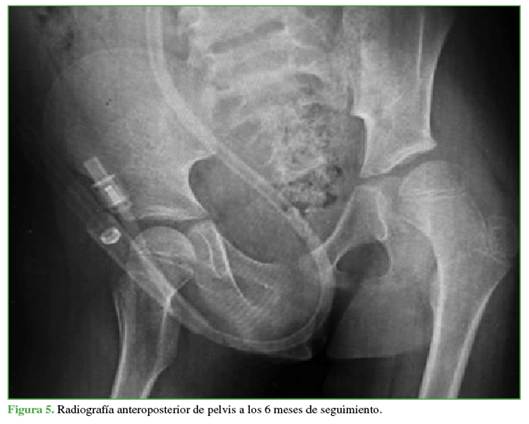

En las radiografías de control a los 3 (Figura 4) y 6 meses (Figura 5), no se visualizaron hallazgos de NAV y también se descartaron otras complicaciones osteomusculares asociadas a la luxación traumática.

Entre las complicaciones descritas se destacan las siguientes: coxa magna, parálisis del nervio ciático, parestesias y NAV de la cabeza femoral.10 En pacientes menores de 18 años, su incidencia tras una luxación aislada oscila entre el 3% y el 15%,17 y es más alta si la reducción fue tardía.18 Por ello, el seguimiento con imágenes es fundamental. Si bien no hay consenso sobre los tiempos ideales; en este caso, se realizaron controles a los 3 y 6 meses, y no se detectó evidencia radiográfica de NAV.

Las radiografías de control no mostraron signos sugestivos de NAV (esclerosis, colapso, quistes, reducción del espacio articular, etc.).22 Estos hallazgos pueden demorar de 2 a 6 meses en hacerse visibles en las radiografías,20 por lo que la temporalidad del seguimiento fue adecuada.